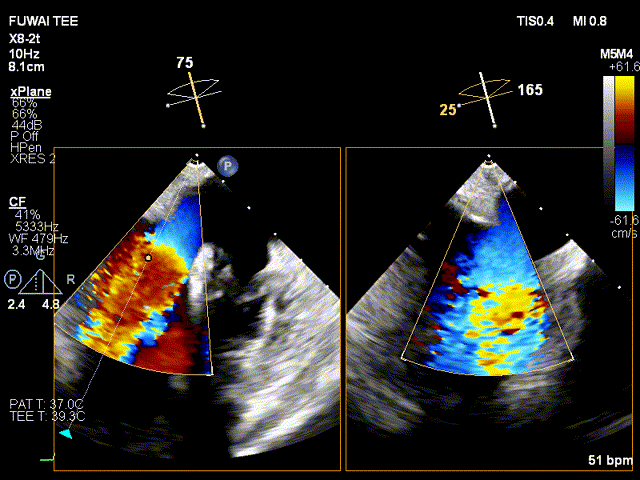

手术团队使用MitraClip®独特的三层双调弯导管,经股静脉穿刺,在食道超声引导下完成房间隔穿刺。穿刺后将导管送入左心房,对准二尖瓣目标位置P2区域。准确捕捉瓣叶,二尖瓣夹释放后,超声显示反流几近消失,患者各项生理指标正常,手术顺利完成。